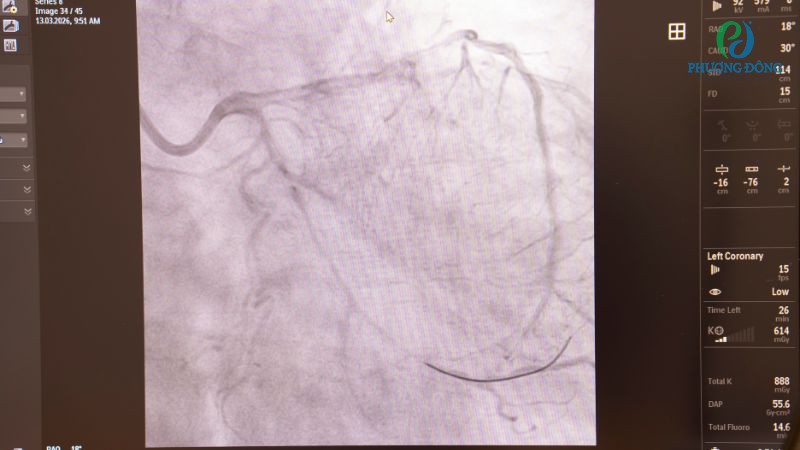

- Bước 2: Dưới hướng dẫn của hình ảnh chụp X-quang liên tục, bác sĩ sẽ luồn một ống thông mảnh qua động mạch để đi vào đoạn bị hẹp hoặc tắc nghẽn.

- Bước 5: Trước khi kết thúc thủ thuật, bác sĩ sẽ kiểm tra lại lưu lượng máu qua động mạch vành nhằm đánh giá hiệu quả can thiệp và đảm bảo stent đặt đúng chỗ.

Hình ảnh mô phỏng quy trình đặt stent tim trong phòng thủ thuật của Bệnh viện Đa khoa Phương Đông